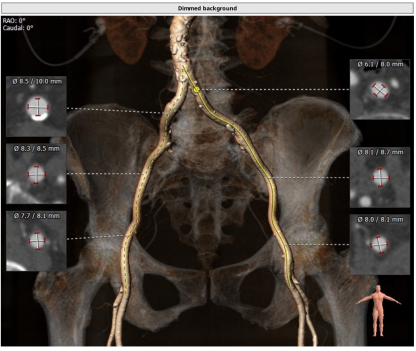

术前CT评估

患者为功能型二叶瓣,重度钙化,左右融合,瓣环平面可见钙化延伸至左室流出道,冠脉高度高,法式窦结构大,心脏角度约51°,心肌增厚。

瓣环平均直径:25.6 mm,左室流出道平均直径:25.4 mm,升主动脉未见明显扩张,心脏角度:51°

钙化积分:832 mm³,重度钙化